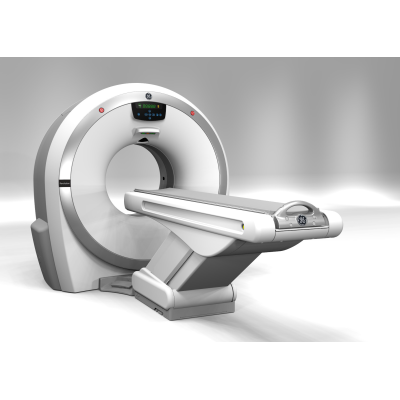

Revolution ACT – это последнее поколение 16-срезовых компьютерных томографов с высокой степенью производительности, удовлетворяющее требованиям к помещению большинства компьютерных томографов, но позволяющее исключить или значительно снизить расходы на подготовку помещений (минимальная площадь помещения 10,1 м2). Данный томограф построен на базе надежной и проверенной технологии, объединяет в себе современные клинические возможности и экономичную стоимость.

| Производитель | GE |

| Класс оборудования | Базовый |

| Количество срезов | 16, 32 |